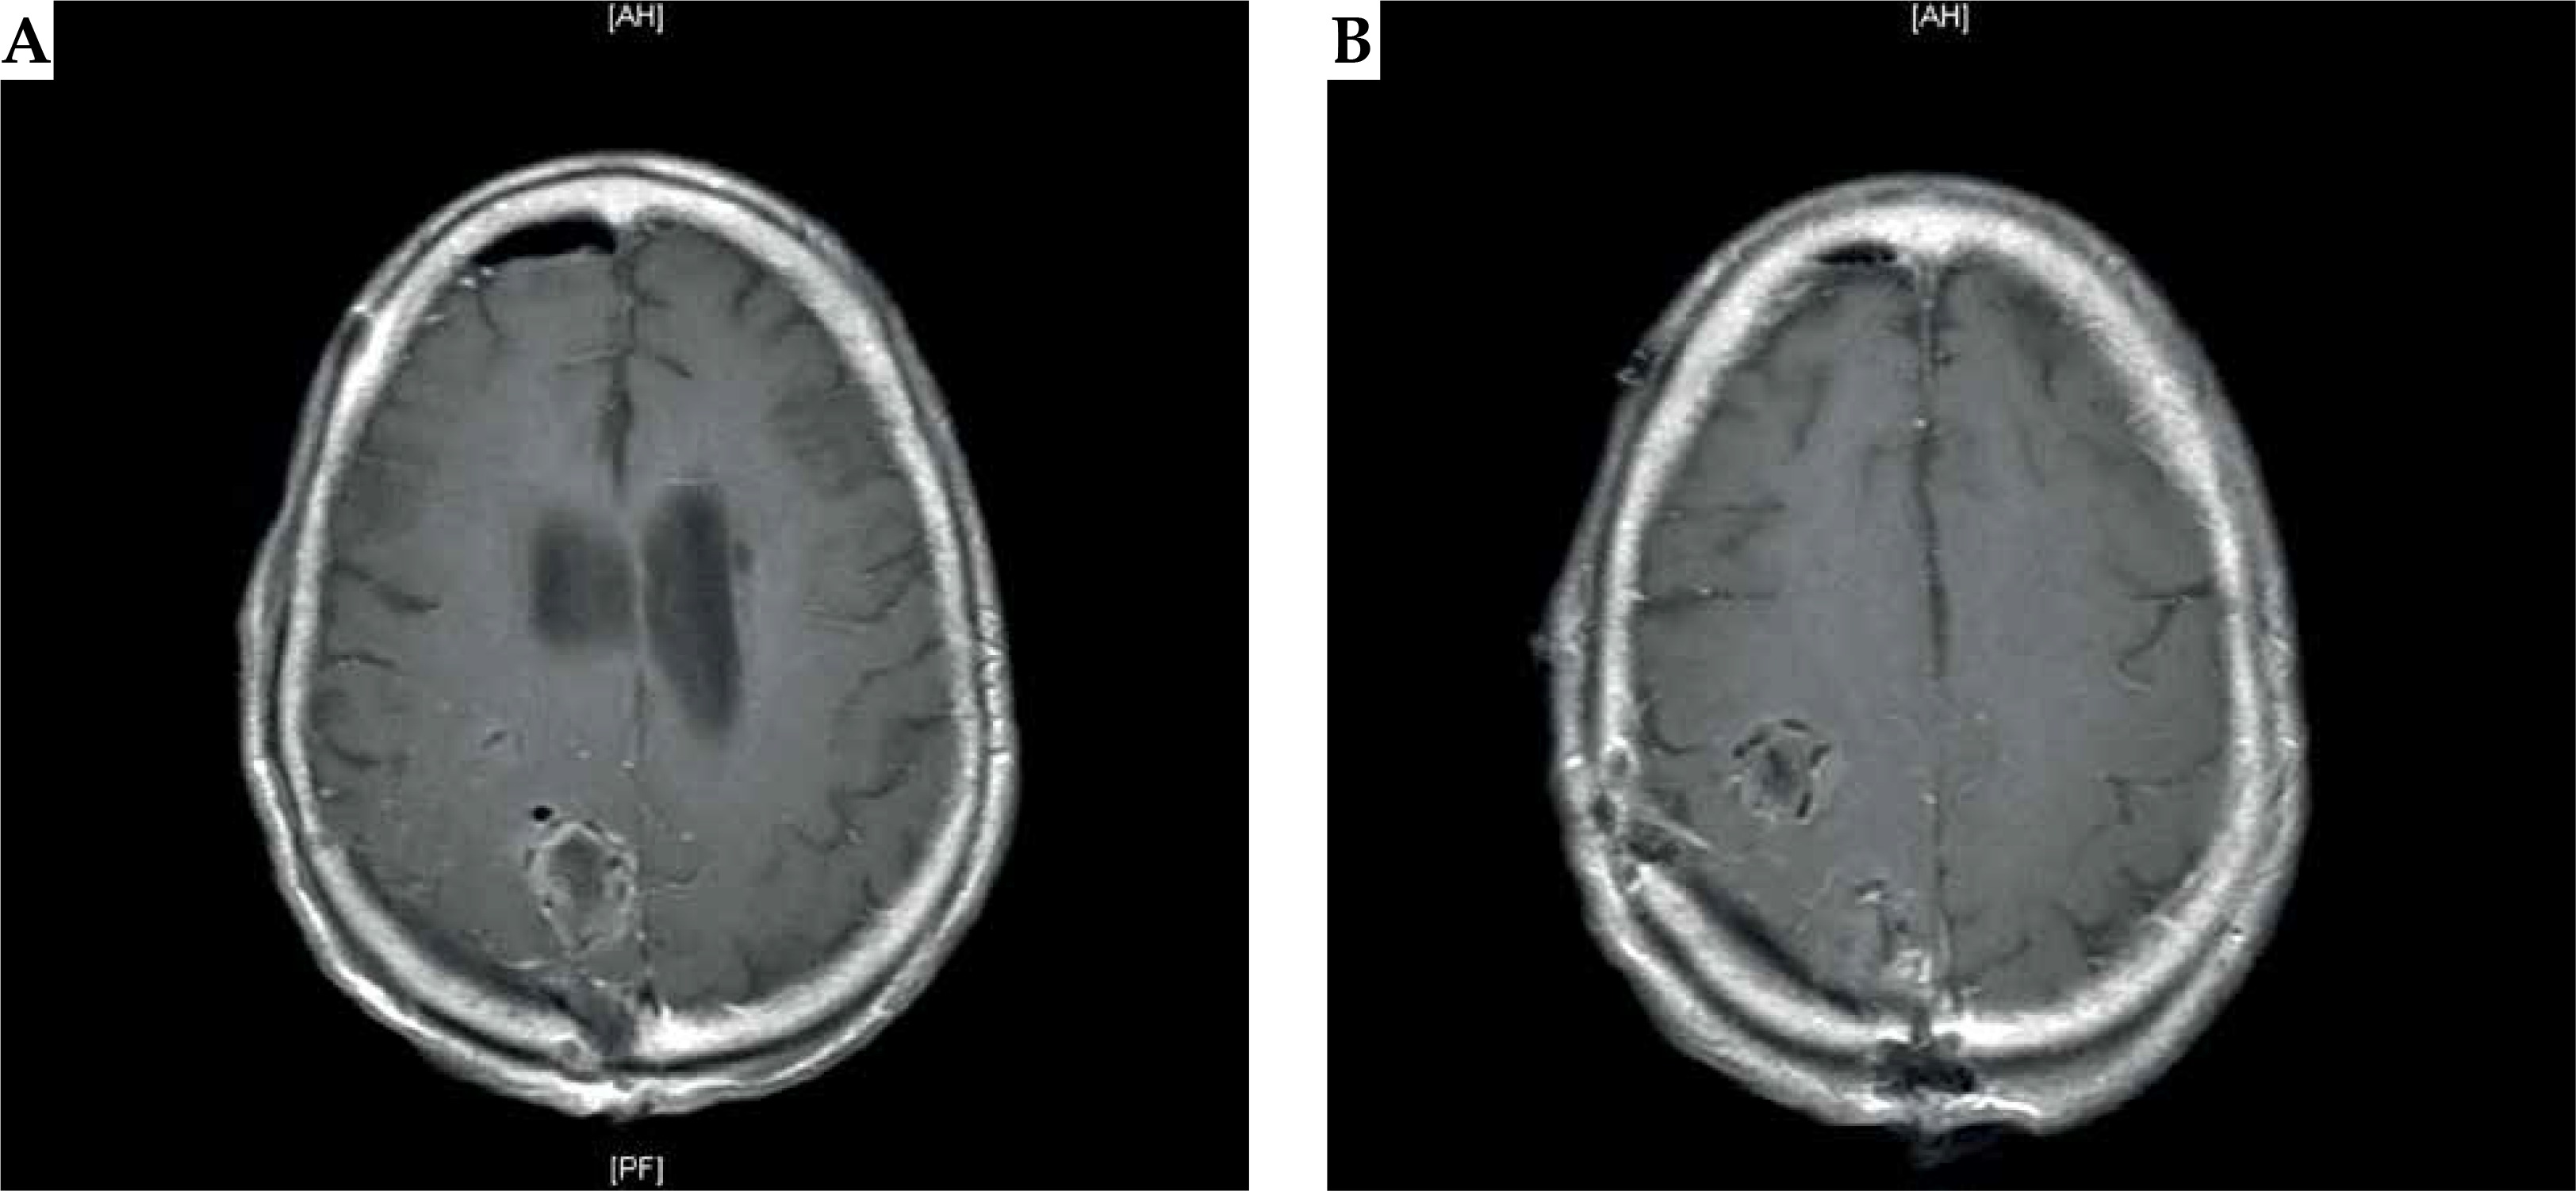

Fig. 1

A) Preoperative MRI of the brain: axial T1-weighted images demonstrate an enhancing anterior posterior right frontal lesion, measuring approximately 1.9 cm × 2.3 cm × 2.4 cm. B) Preoperative MRI of the brain: axial T1-weighted images demonstrate an enhancing posterior right parietal lesion measuring approximately 2.7 cm × 2.2 cm × 2.9 cm